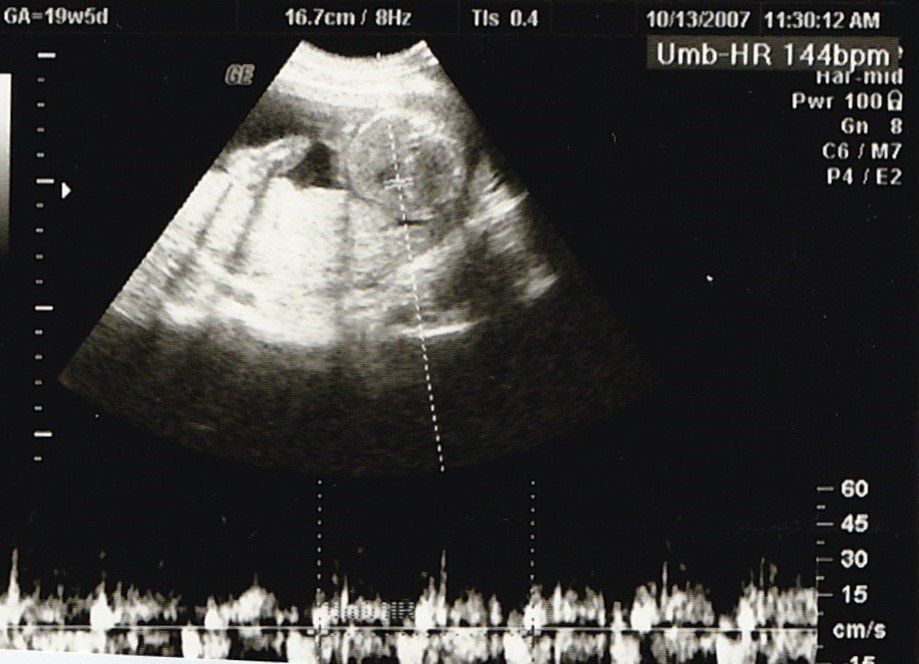

妊娠19週目のエコー写真

安定期に入り、検診のたびに体重や血圧を測るようになりました。前回の検診時から、8~10kgの増加が目安と言われていましたが、妊娠15週から19週の間ですでに1.3kg増。強い食欲と眠気に勝てない毎日に危機感が募り、マタニティーヨガ、マタニティービクスを開始しました。